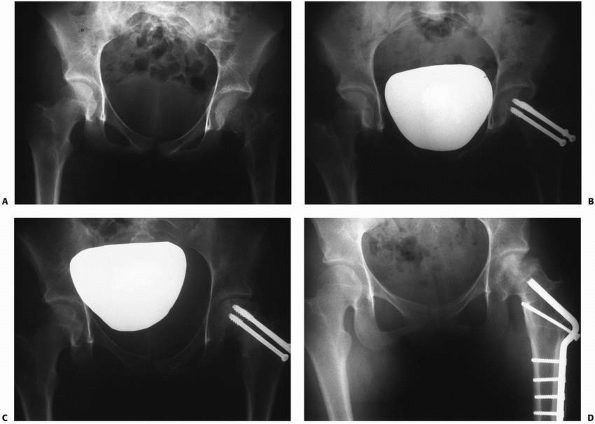

|  |

| FIGURE 21-11 A. A 14-year-old girl with a type II fracture of the left femoral neck. B. After fixation with three cannulated screws. C. AVN with the collapse of the superolateral portion of the femoral head. D. After treatment with valgus osteotomy. |